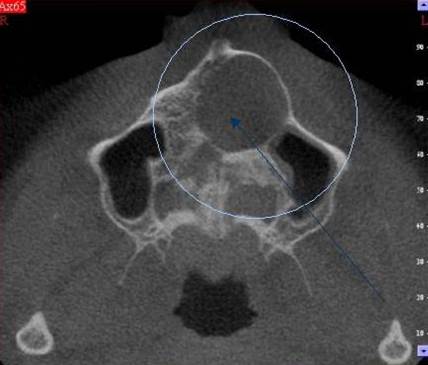

3D DVT - NewTom

Je speciální zubní digitální tříprostorový tomograf (3D), který umožňuje na základě jediného

snímkování vytvořit všechny typy RTG zobrazení, které jsou pro lékaře potřebné. Díky používané technologii tzv. „kuželového paprsku“ a speciálním senzorům je

výrazně zmenšená dávka záření - o více jak 80% proti klasickému CT vyšetření. To je významné zejména u dětí. Pomocí tohoto přístroje je možné zjisti skutečnou situaci v čelistních kostech pacienta tedy množství kosti - můžeme změřit skutečnou šířku i výšku kosti, i kvalitu kosti (hustotu) v místě uvažované implantace. 3D (tříprostorové) zobrazení umožňuje zvýšit prostorovou představu operatéra ještě před vlastní operací a zároveň pacientovi lépe objasnit a ukázat oblast plánovaného zavedení implantátu.

Pacient „neumí číst“ RTG snímky, ale díky 3D zobrazení vidí „svoji skutečnou čelist“

- např. jak je nízká či úzká, vidí průběh nervu nebo velikost čelistní dutiny, což mu umožní i pochopení nutnosti v některých případech provést pomocné zákroky ještě před vlastním zavedením implantátu (viz. kostní štěp, sinus lift, kostní granulát...).

Vyšetření pomocí tohoto přístroje používáme i ve stomatochirurgii (zlomeniny čelistí, zuby moudrosti, cysty, onemocnění čelistního kloubu), ortodoncii (retinované zuby, nadpočetné zuby), parodontologii atd.